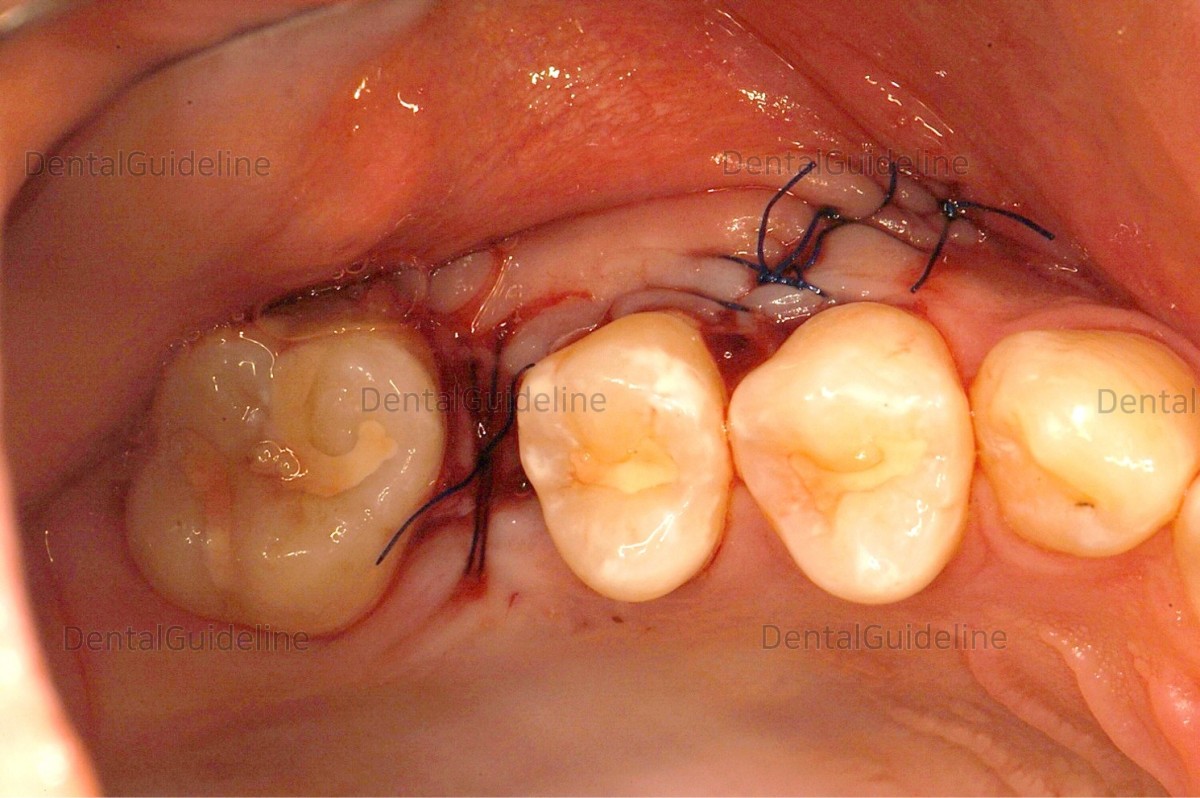

11. suture.

![]()